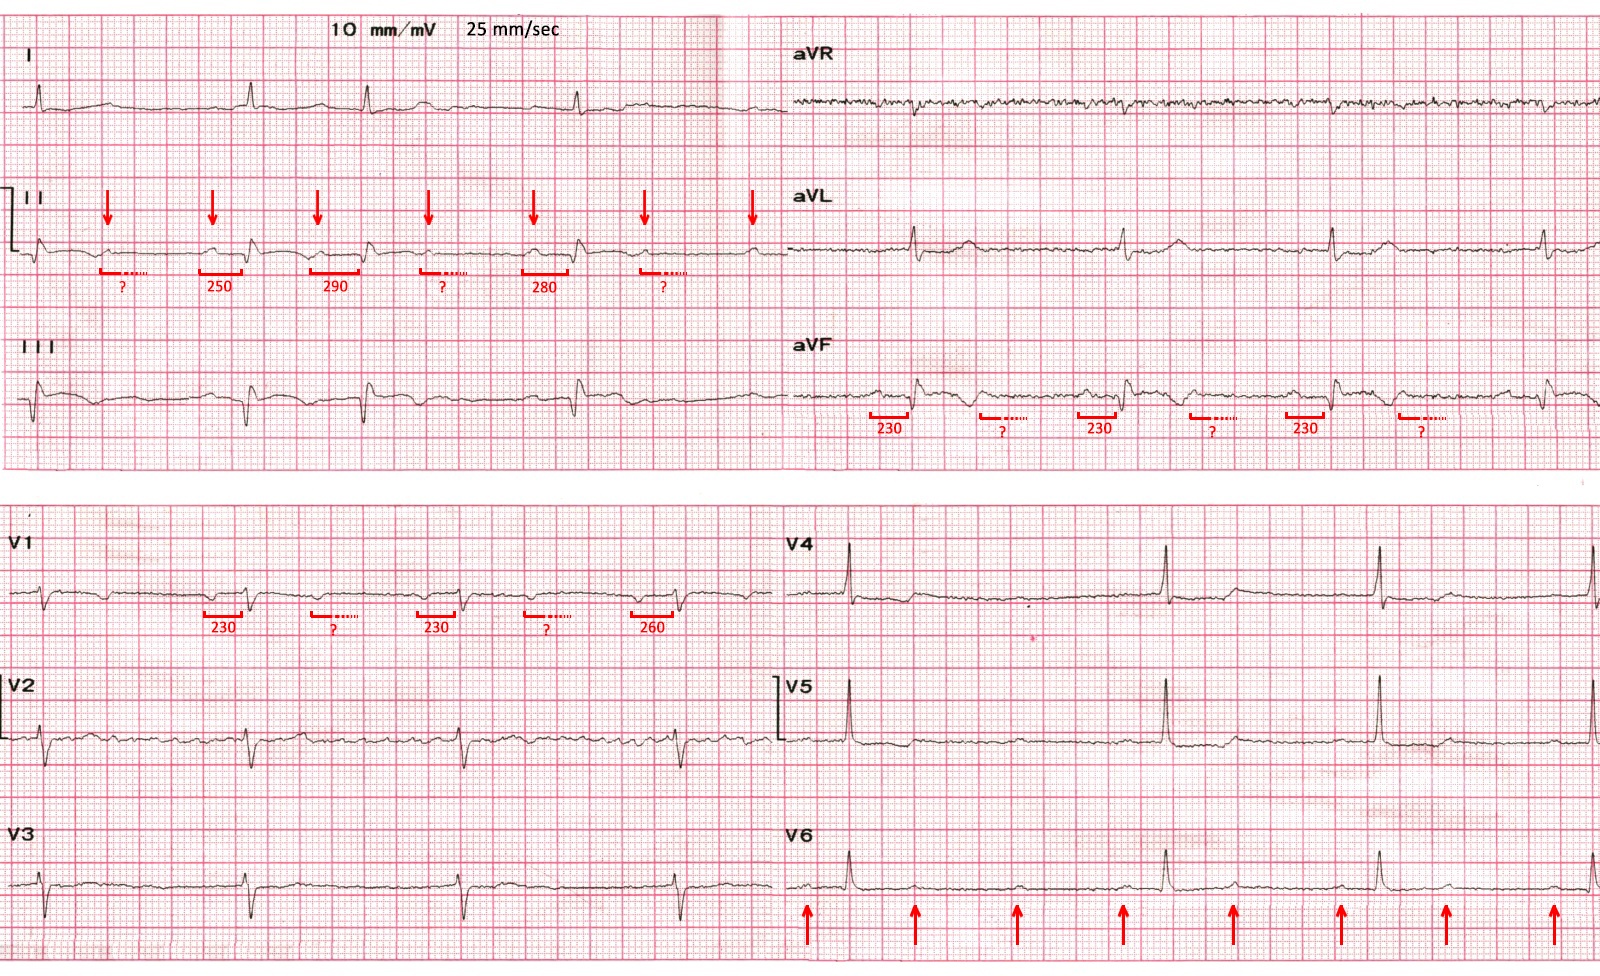

ЕКГ (9 день):

- Мінімальна елевація ST і початок формування негативних Т у ІІ, ІІІ, aVF.

- AV-блокада ІІ ступеню трьох різних типів:

- у відведеннях I-II-III зафіксовано наростання PQ з 250 до 290 мсек із подальшим випадінням кожного другого комплексу (отже, АВ-блокада ІІ ст. типу Mobitz-1)

- у відведеннях aVR-aVL-aVF та V1-V2-V3 - класична АВ-блокада ІІ ст. типу 2:1

- у відведеннях V4-V5-V6 - короткий епізод АВ-блокади ІІ ст. високої градації - коли випадає більше ніж один QRS поспіль.

- Незважаючи на середню ЧСС нижче 50 уд./хв. самопочуття хворого було задовільним, навантаження пов’язане з самообслуговуванням виконував без скарг, тому враховуючи швидку позитивну динаміку ЕКС на цьому етапі не ініціювали.